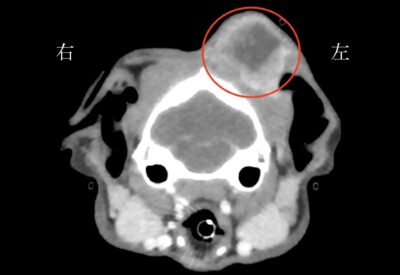

CT検査と組織生検(できものの一部を採取する検査)の結果、できものは扁平上皮癌であり、耳周囲にも浸潤していましたが、水平耳道(鼓膜のある耳の奥側)までは浸潤していませんでした。

CT検査を参考に今回は赤丸で囲んだ範囲を切除することとしました。